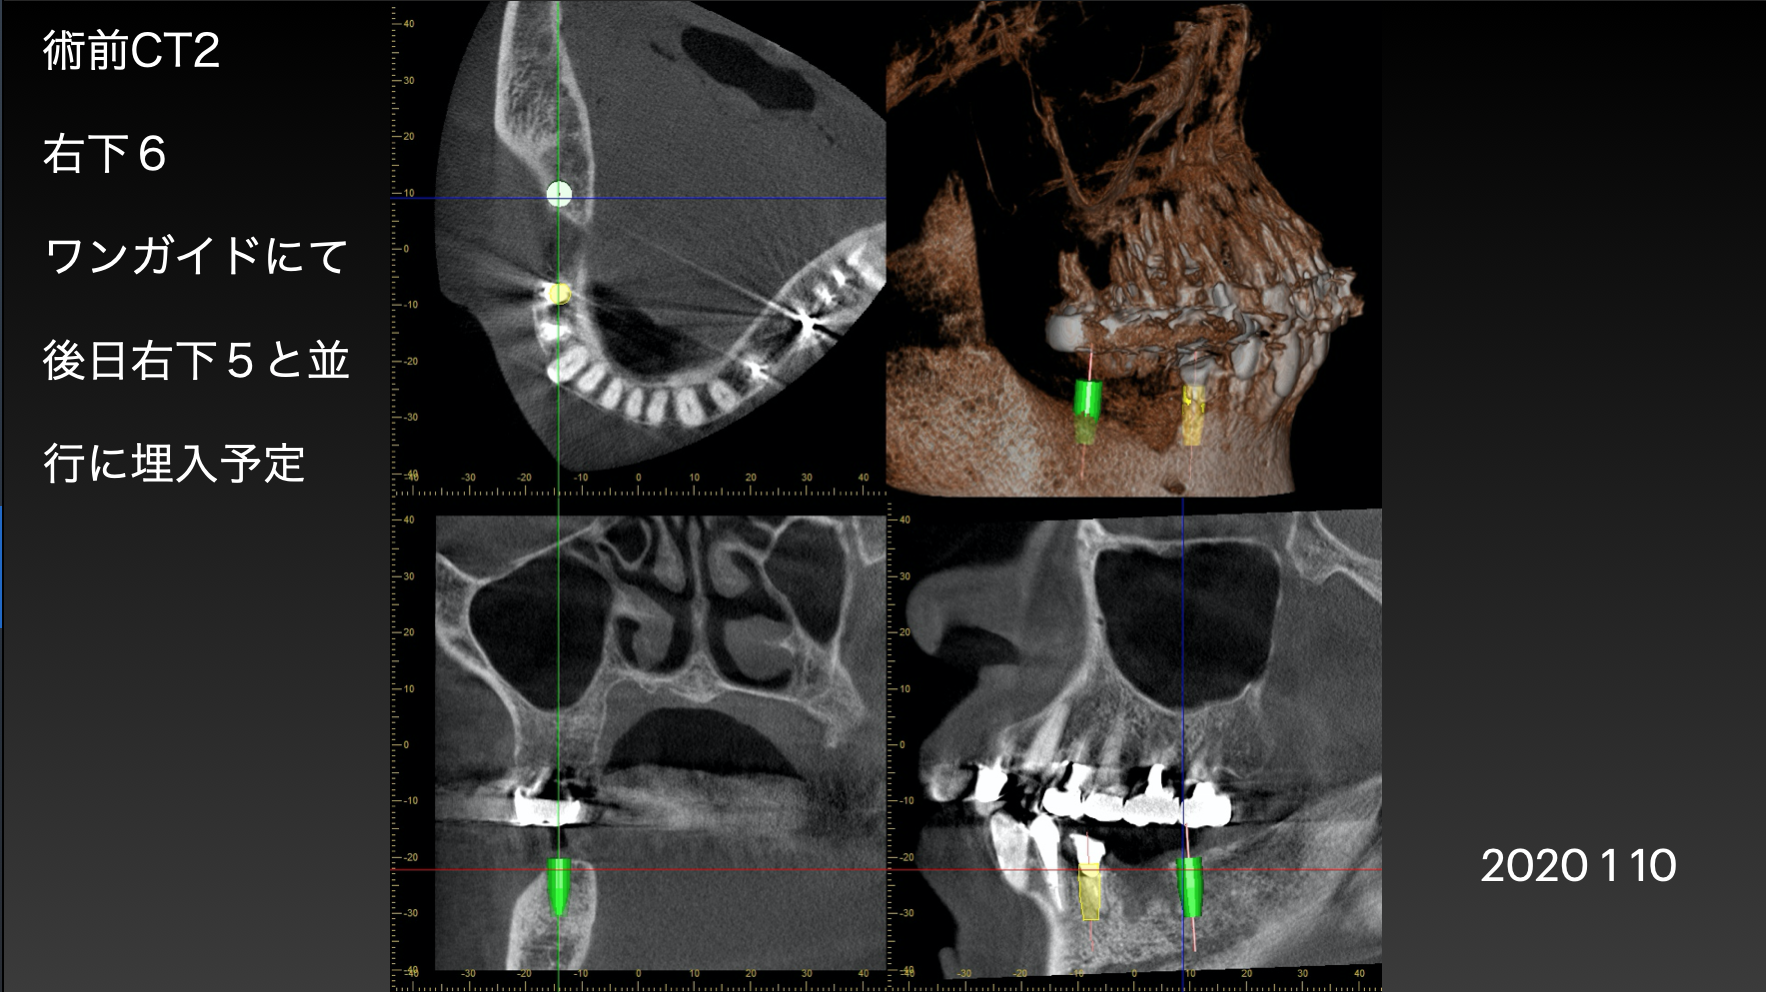

緑が大臼歯用インプラント、黄色がまだ歯が残っている所にいれる小臼歯用インプラントです。(シュミレーション)

インプラント抜歯後即時埋入ができるかどうか判断します。歯の根っこの形によって、インプラントの太さや長さを変えます。また、この画像で抜く予定の歯の周囲に膿みや感染病巣がある場合は、即時でなく通常の手術プランに変更します。

この症例は2本のインプラントを並行に入れなければならない為、オーダーメイドの手術用インプラントガイドを準備しました。